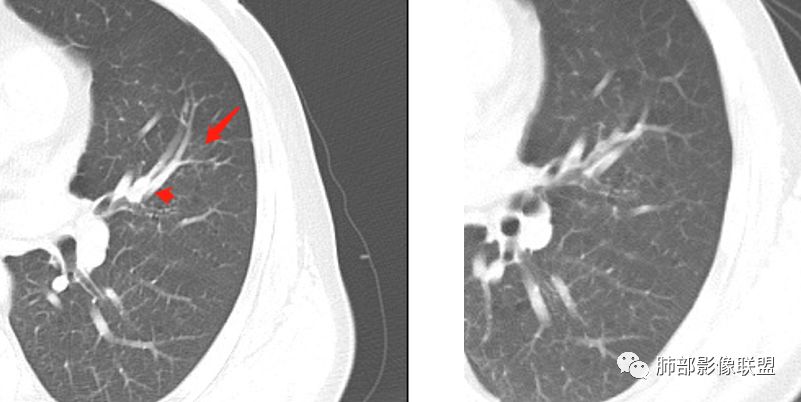

左肺上叶舌段支气管管壁略增厚 间隔一年 管壁增厚明显 向腔外突出形成结节 管腔闭塞 远端片状及斑片影 纵隔淋巴结增大 肺气肿背景 考虑鳞癌伴阻塞性炎症可能

前次片2016年4月20相应位置就有小点状病灶,2017-5-15呈结节影改变,边界膨隆,远端阻塞炎性改变,考虑肺癌,鉴别炎性结节!

老年男性,咯血1月,肺气肿背景,左肺上叶舌段见沿支气管走行分布结节,呈葫芦样改变,左肺门淋巴结肿大明显,首先考虑恶性病变,小细胞癌可能

常规腔内病灶引起远端炎症:

1、肿瘤,良性、恶性?短时间出来——恶性

2、炎性,结核、真菌多见,但是表面膨隆、光滑,不太支持,放待排

3、异物、痰栓,附近的结节不支持,最好有密度测量、强化情况

就目前的资料:我支持恶性肿瘤,待排异物

常规下一步:支气管镜、增强扫描

晨读结果:鳞状细胞癌